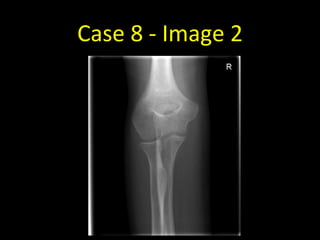

Case 8 - Image 1

Case 8 - Image 2

Case 8

• Not all fractures are visible on

radiographs, particularly in the

acute setting

• There may however be signs of

the fracture in the surrounding

soft tissues

• Remember, fat allows the

transmission of a relatively large

number of x-ray photons and

therefore appears dark

• Note the two triangles of fat anterior

and posterior to the distal humerus

• These are the fat pads that have been

displaced by fluid in the elbow joint

• In practice, this is presumed to be due

to a radial head fracture although the

fracture line is not visible